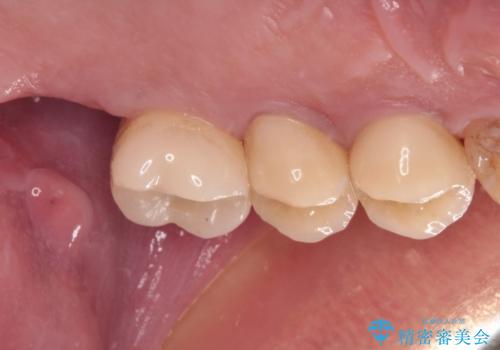

根管治療を行ったままの奥歯 オールセラミッククラウンによる補綴治療

- 以前根管治療を行い、クラウンにする必要があると言われたものの、そのままに放置してしまったとのことで来院された患者様です。

根管治療を行った歯には特に症状がないため、速やかにオールセラミッククラウンにて補綴治療を行うこととしました。

補綴治療前は食後はいつもものが挟まっていたそうですが、補綴治療後はものが挟まる悩みから解放されたとのことでした。